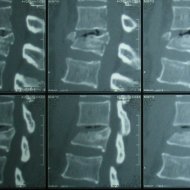

Omurga Kırığı

Omurga kırıkları osteoporozun olmadığı sağlıklı kişilerde trafik kazası ya da yüksekten düşme gibi yüksek enerjili travmalar sonucu oluşur. Eğer omurilik basısına neden olursa kısmi ya da tam felç ile sonuçlanabilir.

Eğer travma ilerleyen dönemde deformiteye yol açmayacaksa veya sinirlere baskı yaparak nörolojik bulguya neden olmadıysa korse ile tedavi edilebilir. Bu amaçla sert polietilen korseler ya da metalden yapılmış çerçeve tipi korseler kullanılabilir. Omurganın ağır zarar gördüğü durumlarda ileride oluşabilecek deformiteyi engellemek için omurganın vida ve çubuklarla sabitlenmesi gerekebilir. Nörolojik bulgu oluşturan bir kemiksel bası varsa, aynı seansta bu bası da ortadan kaldırılabilir.